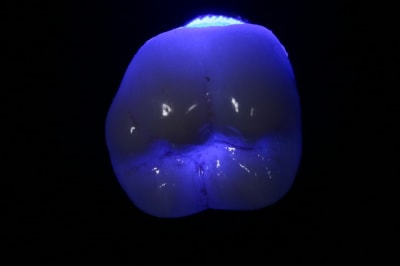

Un résultat un peu mieux aujourd'hui... mais en Emax monobloc !

Ça fait 12-15 ans que je fais uniquement du céram de pré-molaire à pré-molaire. Pour faire une limite supra gingival invisible ou presque, il faut un bon labo, des photos (souvent) et un bon choix de couleur (couleur de la racine et des dents voisines).

La molaire en E-max est bien. C'est le même labo ?

Ouep ouep ouep, pas mal la molaire...

Etonnant que le même labo en soit à l'origine...

c'est une question de labo :

ici 3 emax, labo habituel.

Super cingulum, par contre sur ce que tu nous montres il y a apparemment une chape en pressée et une stratification. N'as-tu pas peur que ça soit un peu limite pour des molaires ?

Z'aime bien E-max (ça se colle, VS zircone qui ne colle à rien)

Z'aime aussi la E-Max style champignon, pas d'IC.

Collé sous digue, c'est très bien.

Dommage pour la dernière photo en bouche, c'est flou !

C'est quoi sur la 7 ? Un vilain Hg ? ;-)

Ton labo utulise une teinte de E-Max très opaque et blanche. Il y a bcp plus naturelle et translucide pour des cas antérieurs, ou quand la couleur finale est moins foncée.

Pour les chappes effectivement mon protho utilise toutes les gammes de teinte et d'opacité selon le cas...

L'opaque comme sur ces molaires permet de faire des couronnes sur ICore. Dans le cas précis, il y avait une molaire avec 1 IC donc il a tout pressé dans le meme berlingo. A noter que meme le noyaux high opacity laisse passer de la lumière...

C'est l'avantage de de l'emax, bcp de choix pour le prothésiste.

Autre exemple avec infrastructure low opacity sur une centrale

Concernant la stratification, j'ai jamais eu d'eclat de ceram sur une emax... il y a une trés forte cohésion entre le noyau et la céram de stratification, contrairement aux autres chappes (zircone notamment...)